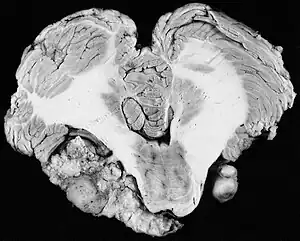

There have been cases of tumors that were actually asymptomatic until very large and at a critical stage. Tumor growth rates are highly variable: some small VSs (perhaps 50%) do not grow at all; some few grow for a time and then shrink; some appear dormant but suddenly grow rapidly. In general, although studies differ, VSs that grow are slow-growing at an average rate of 1.2 to 1.9 mm per year. IAC tumors that grow beyond 1.5 cm in diameter expand into the relatively empty space of the cerebellopontine angle, taking on the characteristic 'ice-cream-cone' appearance seen on MRIs. As 'space-occupying-lesions,' the tumors can reach 3 to 4 cm or more in size and infringe on the facial nerve (facial expression) and trigeminal nerve (facial sensation). Hearing loss and spells of vertigo may occur. Very large tumors are life-threatening when they press on the cerebellum or cause brainstem compression. Late symptoms of very large VS include headache, nausea, vomiting, sleepiness, mental confusion and eventually coma.[4][5]

In the early 1900s the mortality rate for VS surgery was in the range of 75 to 85%. Surgeons typically delayed invasive intervention as long as possible as a last resort. Harvey Cushing (1869–1939) is known as 'the father of neurosurgery for VS.' His basic study published in 1917 was entitled Tumors of the Nervus Acusticus and the Syndrome of the Cerebellopontine Angle. Cushing perfected the retrosigmoid surgical approach, and by doing suboccipital craniotomy and subtotal removals he was able to reduce mortality to 4% by 1931. Cushing worked at Brigham Hospital in Boston. An equally famous specialist for VS at Johns Hopkins in Baltimore was Walter E. Dandy (1886–1946), a former pupil of Cushing who advocated total tumor removals. In 1931, he reported a complete removal with preservation of the facial nerve.